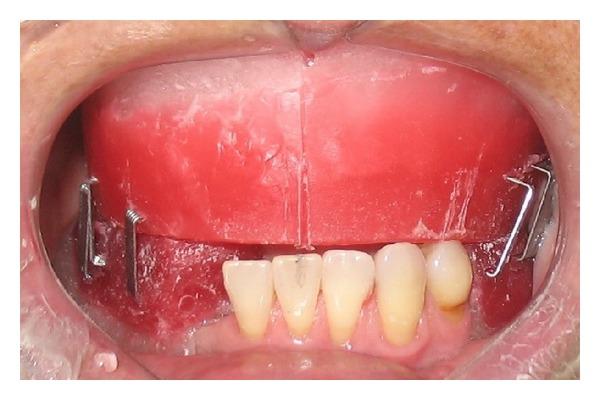

In mandibular edentulous patients, treatment based on immediate loading with rigid splinting in the mandible is well accepted; however, it is cost and time dependent, which sometimes limits this type of rehabilitation. To overcome these problems, the technique of immediate loading using a semirigid splinting extension system has been developed. Its advantages include low cost, technical feasibility, and reduced clinic time. This clinical report presents the applicability and the predictability of semirigid splinting of implants in the mandibular arch of an edentulous patient using a distal extension bar prosthesis system.

在下颌无牙患者中,基于下颌即刻负重并采用刚性夹板固定的治疗方法已被广泛接受;然而,这种方法成本较高且耗时,有时会限制此类修复方式的应用。为克服这些问题,已开发出使用半刚性夹板延伸系统进行即刻负重的技术。其优点包括成本低、技术可行性高以及临床时间缩短。本临床报告介绍了在一名无牙患者的下颌弓中使用远端延伸杆假体系统对种植体进行半刚性夹板固定的适用性和可预测性。